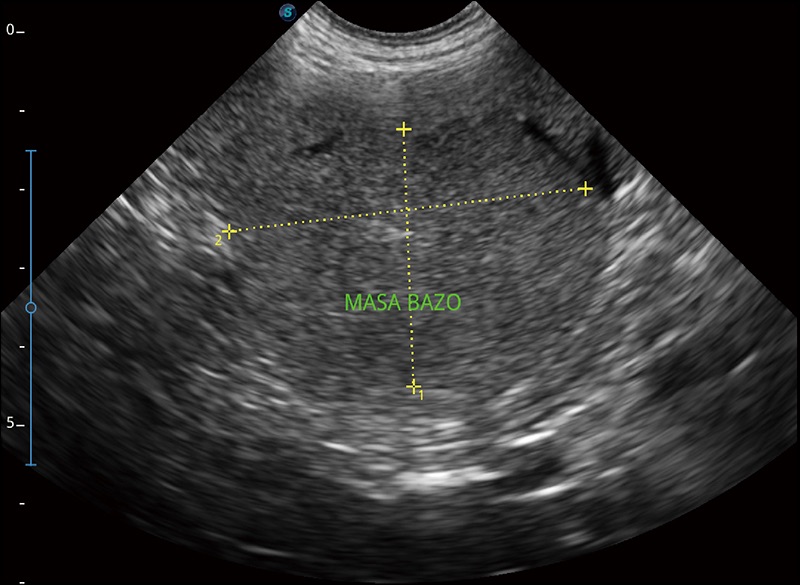

可实时观察感兴趣区域和病变位置